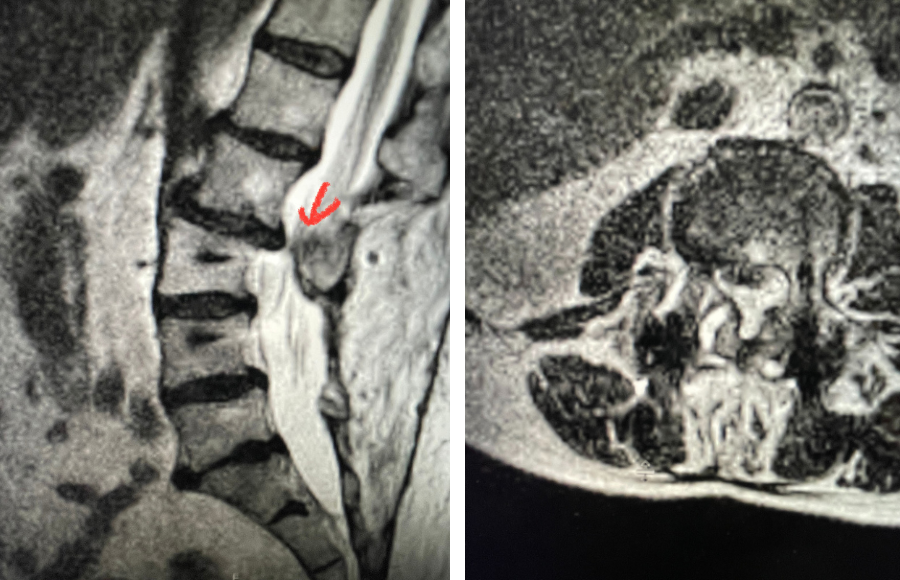

Fig 1: Plain X-rays demonstrating a grade 1 L45 spondylolisthesis with dynamic translation of approximately 4 mm (arrow).

Plain lumbar x-rays were done with flexion/extension views. Surprisingly the patient had 4 mm of anterior translation and slight angulation in flexion (Fig 1). This was unexpected because in degenerative spondylolisthesis the patient more commonly has auto stabilized by formation of stabilizing arthritic structures and has no motion on dynamic x-rays. However, approximately 20% of patients will have some degree of translation on flexion-extension x-rays with degenerative L4-5 spondylolisthesis. Because she had failed all means of conservative management, it was felt that the patient would benefit by a lumbar decompression and instrumented fusion because of the acute instability demonstrated on x-rays and her age.